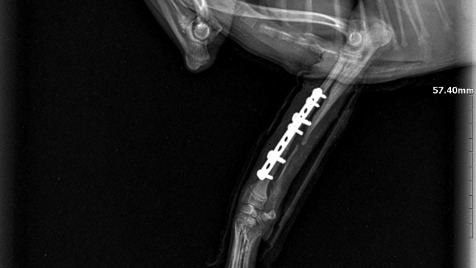

Tosia jest po operacji. Ma wstawiona płytkę i 6 śrub. Teraz czekają nas kontrolę rtg co 3 tygodnie i będziemy obserwować jak łapka się zrasta. Dziękujemy wszystkim za dobre słowo i wpłaty 🙂